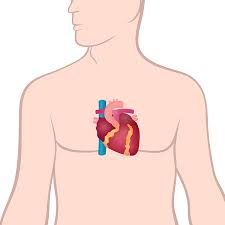

- 심장은 흉강(thorax) 중앙에 위치하며, 흉골(sternum) 바로 뒤, 좌측으로 살짝 치우쳐져 있습니다 :contentReference[oaicite:1]{index=1}.

- 정확히는 흉골 기준 좌측 2/3, 우측 1/3이 차지하며, 양쪽 폐 사이에 있는 중간격(mediastinum)에 포함돼 있습니다 :contentReference[oaicite:2]{index=2}.

- 흉골 바로 뒤·좌측에 위치해 늑골이 물리적 보호를 제공하지만, 흉부 충격 시 손상 위험도 있습니다.

- 심장이 폐 사이에 위치해 폐와 연결된 혈관 구조가 복잡하게 얽혀 있으며, 심폐 기능이 조화롭게 이루어집니다 :contentReference[oaicite:18]{index=18}.